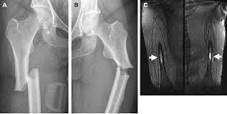

**非典型股骨骨折的图像**

这种类型的骨折在机构的最强骨,股骨轴,其位于所述大腿之一发生。发生的正下方最髋部骨折和某些特性的股骨颈定位这些骨折是骨增厚,前驱疼痛和位置,这是在股骨骨的顶部2/3。

典型的x射线通常不显示出股骨的应力性骨折,所以要执行的MRI或CT扫描的需要,如果断裂不上的X射线显示。断裂必须从低能量创伤其中骨断裂的下降之前,在大多数情况下。如果核医学测试表明这种类型的骨折,那么你将有AFF的诊断。